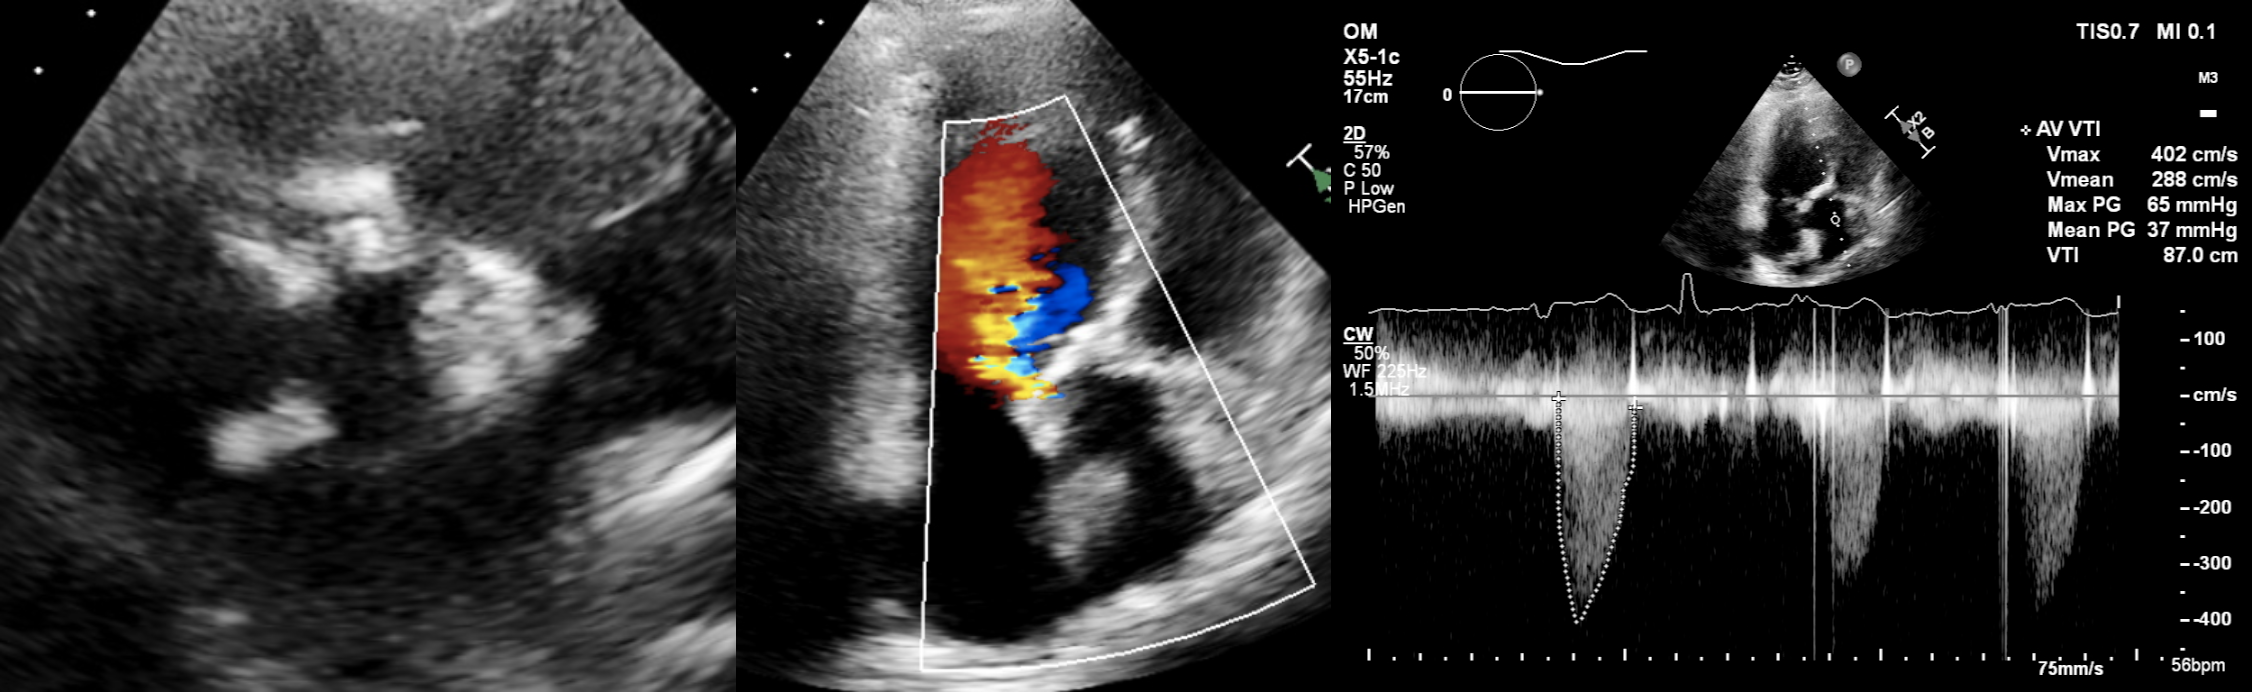

Relevant Test Results Prior to Catheterization

Her echo showed LVEF 41%, severe bicuspid aortic stenosis with fusion RCC/NCC, Mean/Max 37/65mmHg, Vmax4.02m/s, AVA 0.8cm2 with mild to moderate aortic regurgitation. Her coronary angiogram and graft study showed patent LIMA-LAD, radial-diagonal grafts, eccentric distal LM disease extending into ostial LAD and non obstructive LCx and RCA disease. The left subclavian artery appeared severely tortuous as well.